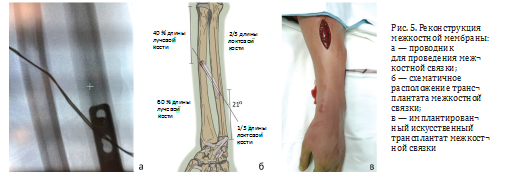

Затем выполнен доступ к средней трети лучевой кости. Через лучевую и локтевую кости проведены по одной спице Киршнера таким образом, чтобы после формирования отверстий для проведения трансплантата угол относительно длинной оси локтевой кости составил примерно 21°, что соответствует вектору силы центрального пучка межкостной мембраны.

Места выхода спиц из кортикальных слоёв, обращенных к межкостной мембране, располагались на 35 % длины локтевой кости и на 55 % длины лучевой кости от их шиловидных отростков, что соответствует анатомии центральной части межкостной мембраны [11]. Через спицы канюлированным сверлом созданы костные туннели. Установлен искусственный трансплантат с пуговицами TightRope (Arthrex) в нейтральном положении предплечья (рис. 5).